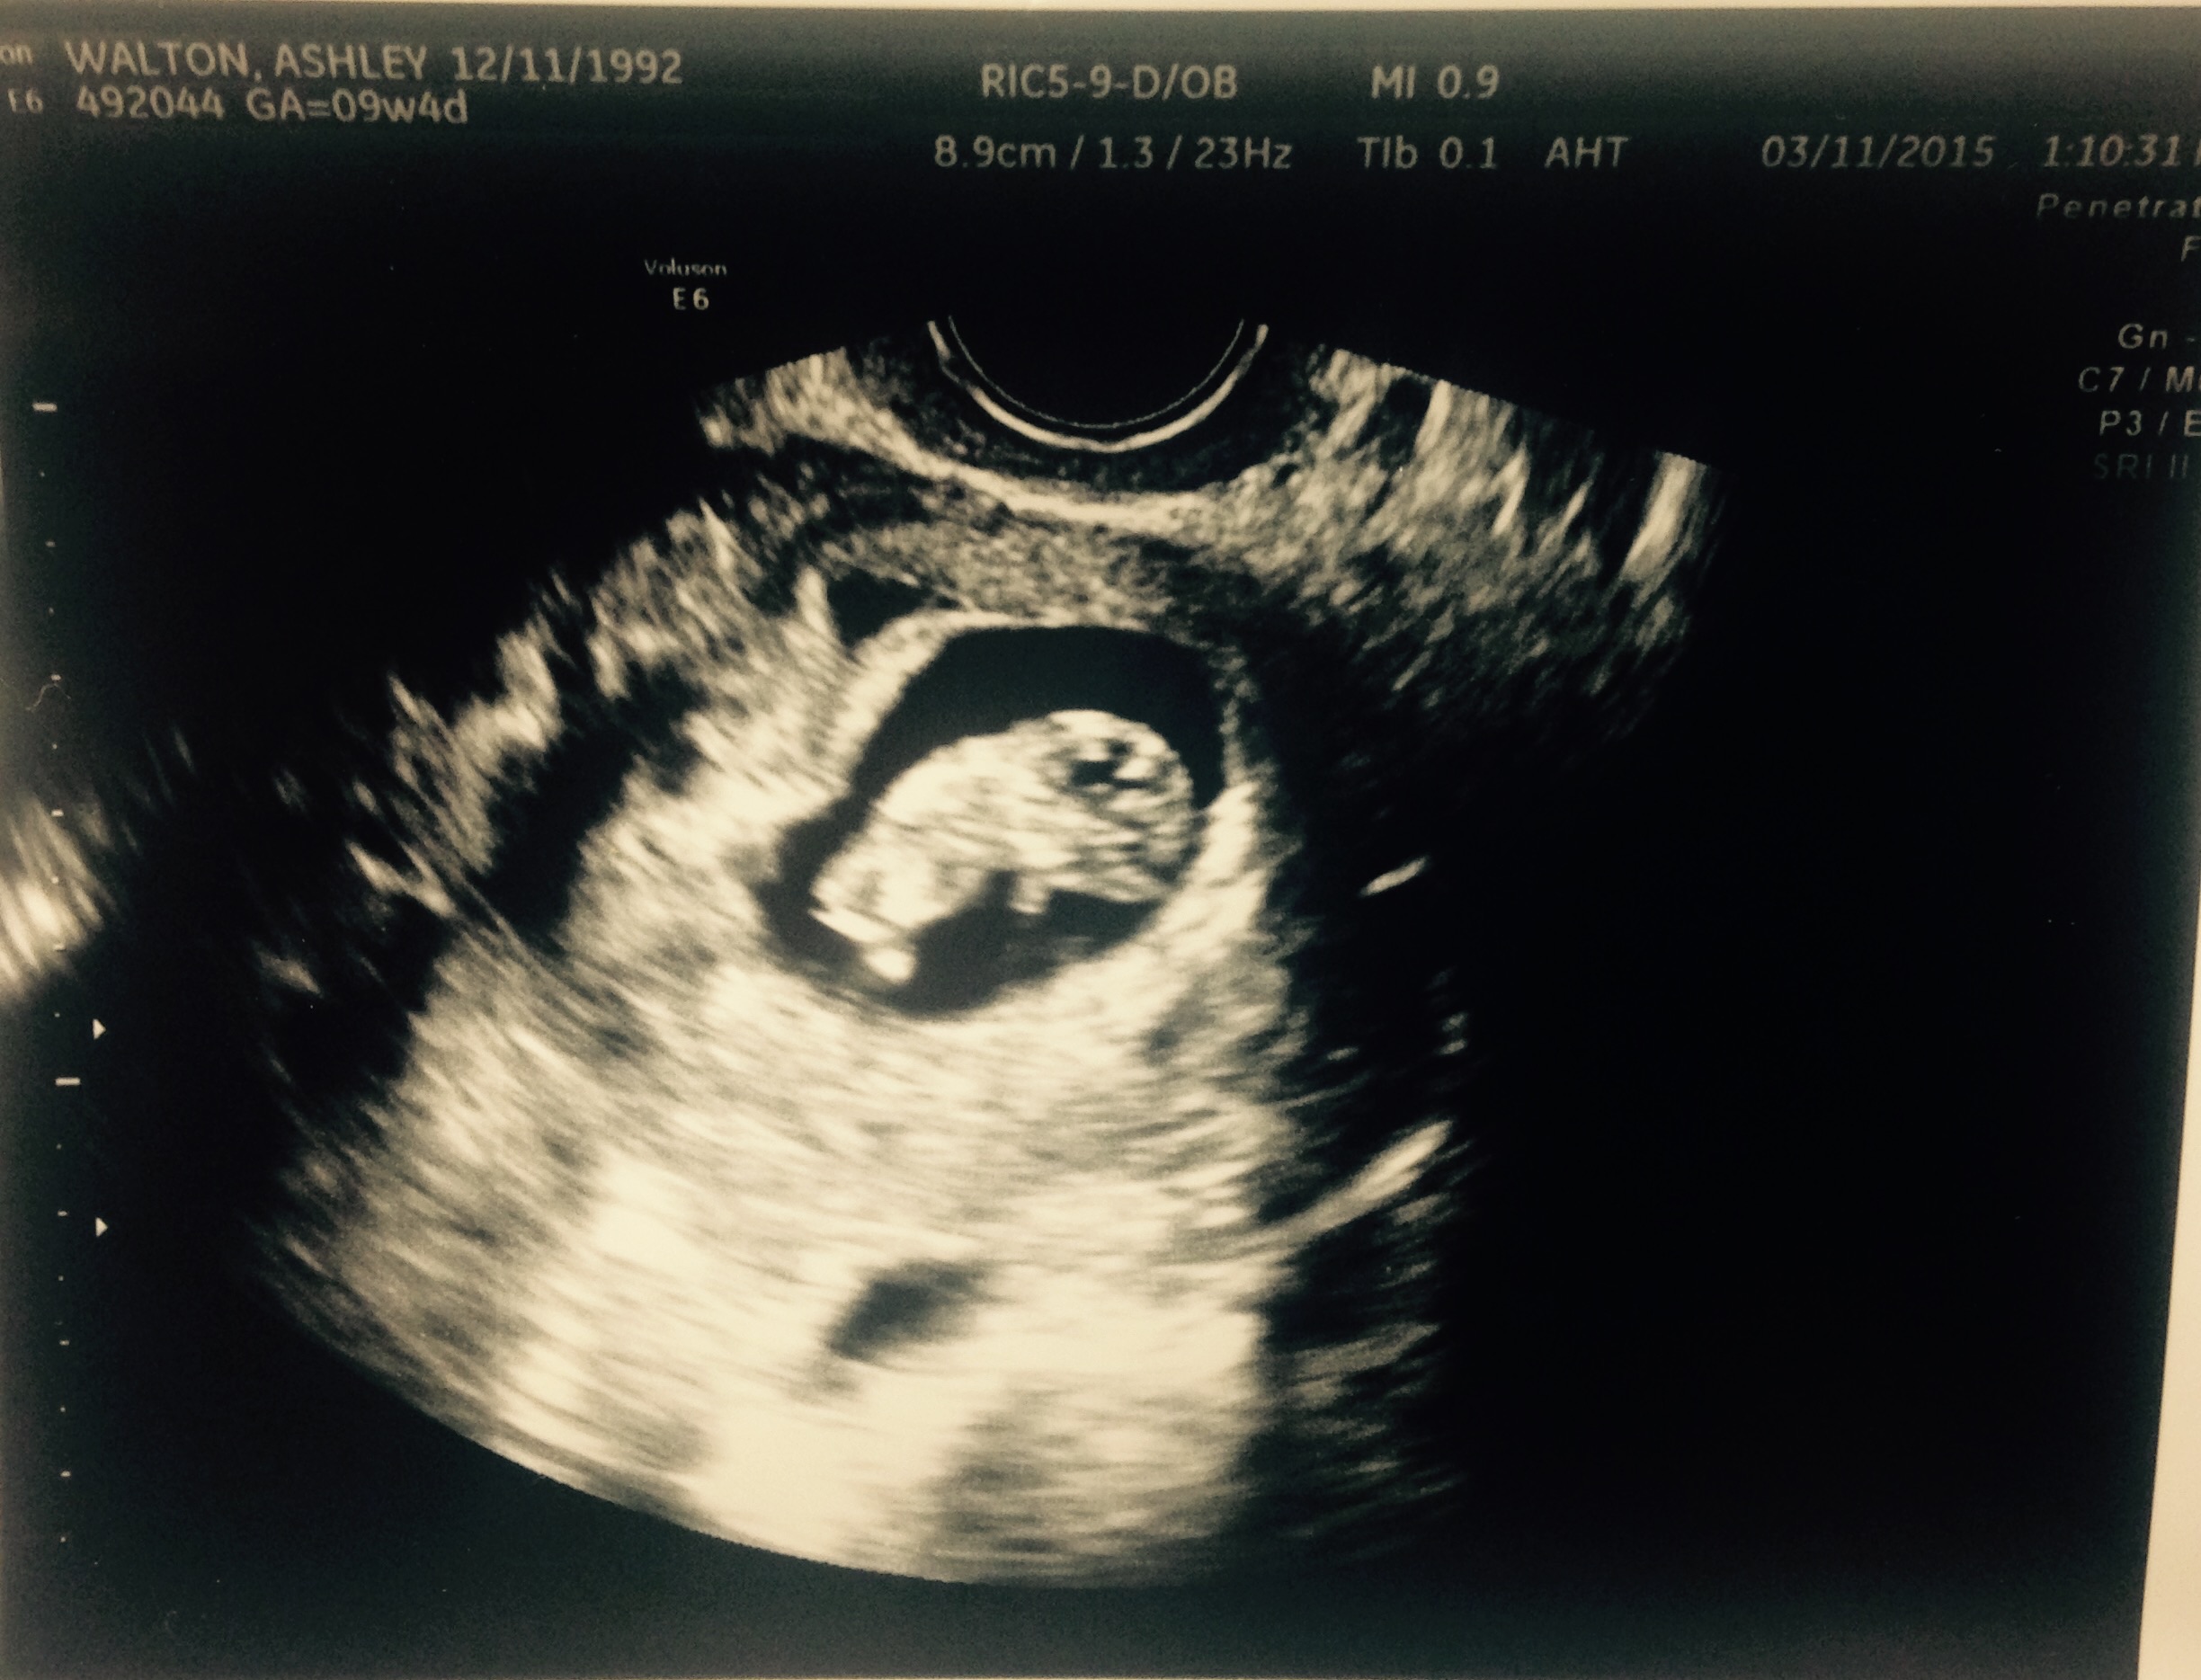

Baby Walton today (3/11) at 9w4d gestational age is +1 day! He even stretched his arm out during the U/S and we saw the heartbeat!! HR is 162 bpm so in love with this tiny thing!!